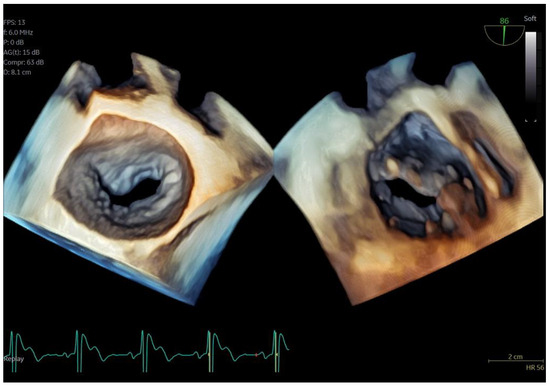

Figure 7.

Secundum ASD closure case; (A) Flexislice method for measurements with both 2D and 4D images, (B) guide catheter through the defect (red arrow), (C) biplane 2D images showing the implanted ASD occluder, (D) 3D volume-−rendered image showing the final result with an ASD occluder.

Figure 8.

LAA closure case; (A) biplane images of the LAA showing the presence of distal thrombus (red arrow), (B) measurements of the ostium and the landing zone with biplane imaging, (C) Biplane images of the implanted AMULET device (red arrow), (D) 3D volume−rendered image showing a view of the implanted AMULET device (red arrow).

Figure 9.

PFO closure case; (A) J wire through the PFO tunnel (red arrow), (B) stiff wire for guidance through the PFO tunnel (red arrow), (C) 3D volume−rendered view of the guide catheter through the PFO tunnel (red arrow), (D) final result with left atrial view of the PFO Amplatzer occluder (red arrow).

In the case of LAA closure (Figure 8, video S3), 3D tools (MPR-flexislice) aided in accurate sizing of the ostium and the landing zone (important for AMULET device), particularly in the presence of distal thrombus where contrast infusion was contraindicated. The final result was satisfactory, with no leakage observed and a stable device placement was confirmed with a tug test.

PFO closure cases (Figure 9, video S2) benefited from the probe’s excellent imaging, enabling precise wire insertion and providing anatomical criteria for device sizing. A bubble contrast study was performed at the beginning and at the end of the procedure for any remaining shunt. The stability of the device was confirmed with a wiggle test. Similarly, in the ASD case (Figure 7, video S1), the probe facilitated visualization of all defect rims and accurate sizing of the oval-shaped defect (with MPR) confirmed with balloon sizing and stop-flow technique and ensured a successful outcome with no residual shunt observed.